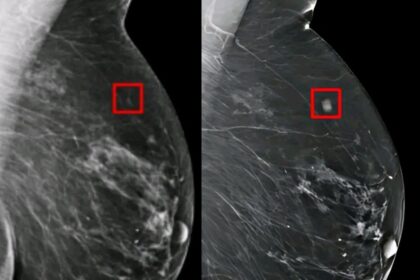

AI ανιχνεύει καρκίνο του μαστού 5 χρόνια νωρίτερα – Νέα εποχή στην πρόληψη

Prima

2 Οκτωβρίου, 2025